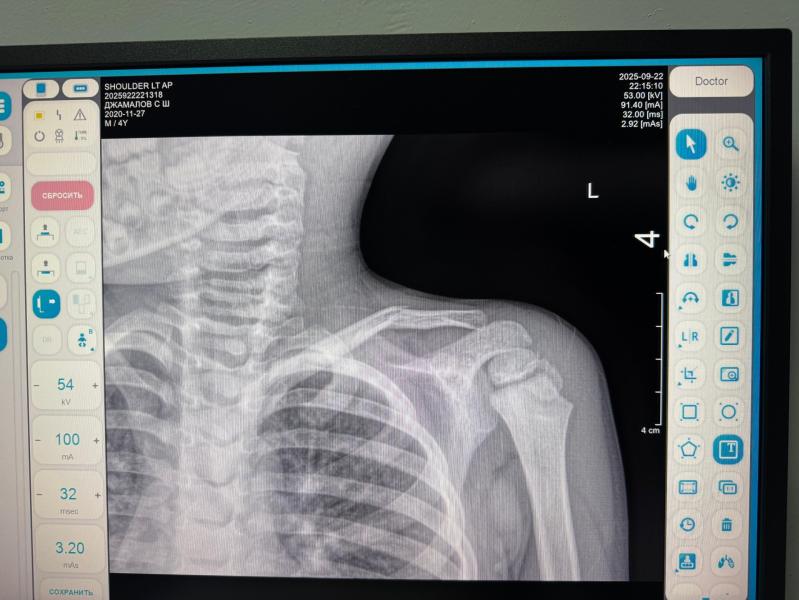

Что делать, если у мальчика сломана ключица и назначили бандаж?

У мальчика сломалась ключица,сказали носить бандаж? Кхи хумма далур дуй цун?

Надкостница целая, быстро срастётся. Бандаж обязательно. Вит Д, кальций можно